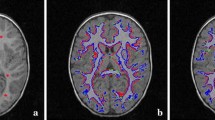

In this paper, we have proposed a new framework to use both PET and CT images simultaneously for tumor segmentation. Our method combines the strength of each imaging modality: the superior contrast of PET and the superior spatial resolution of CT. We formulate this problem as a Non-Local Active Contours (NL-AC) based-variational segmentation framework incorporating Belief Functions (BFs). The proposed method used all features issued from both modalities (CT and PET) as a descriptor to drive the NL-AC curve evolution. The new segmentation framework allows us to incorporate in the same framework heterogeneous knowledge in order to reduce the imprecision due to noise poor contrast, weak or missing boundaries of objects, inhomogeneities, etc. The proposed method was evaluated on relevant tumor segmentation problems. The results showed that our method can effectively make use of both PET and CT image information, yielding segmentation accuracy of 81.52% in Dice Similarity Coefficient (DSC) and the Average Symmetric Surface Distance (ASSD) of 1.2 ± 0.8 mm, which is 10% (resp., 16%) improvement compared to two state of art segmentation methods using the PET (resp., CT) images.